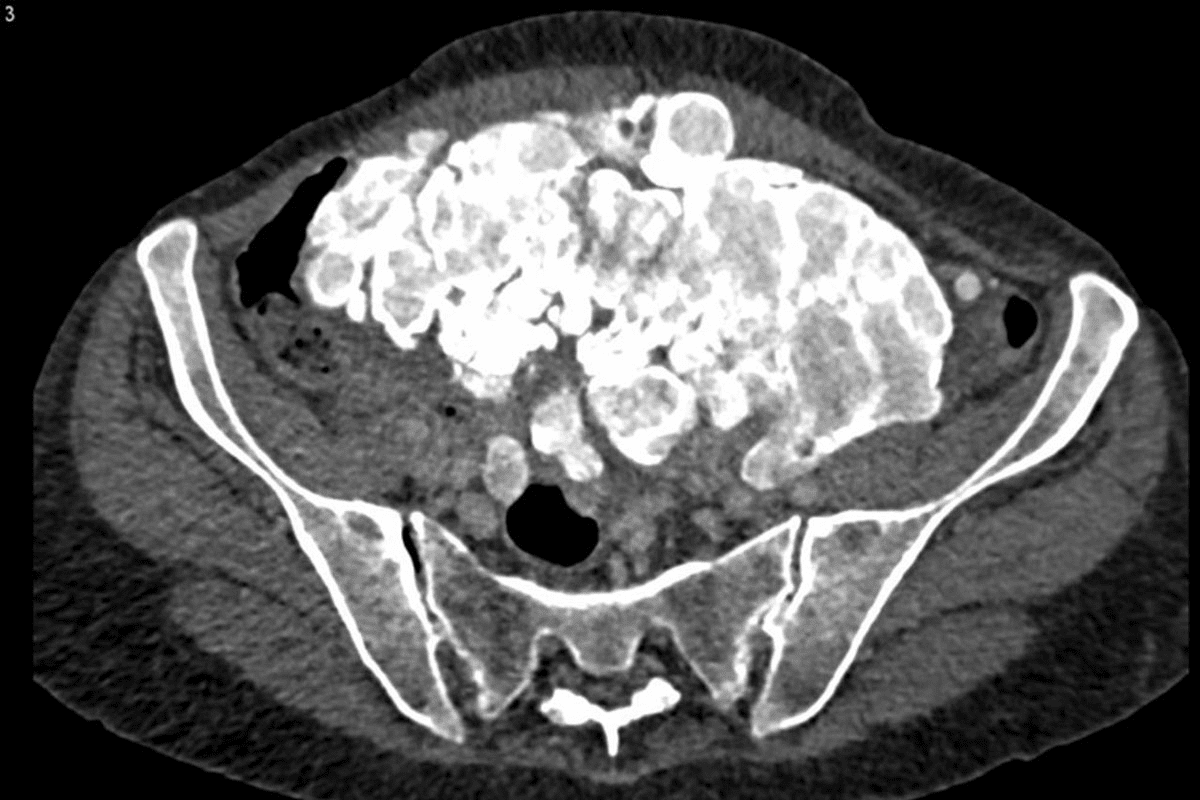

Benign Conditions That Mimic Malignancy on PET Scans

Some non-cancerous conditions can look like cancer on PET scans. Says it’s important to be careful when reading these scans. This helps tell the difference between harmless and harmful conditions.

Granulomatous Diseases and Sarcoidosis

Granulomatous diseases, like sarcoidosis, can also show up as FDG-avid on scans. This makes it tricky to tell if it’s cancer or not. Sarcoidosis can look like lymphoma or other cancers because it forms granulomas that take up FDG.

The fdg avidity in these diseases shows we need a detailed approach to diagnosis. When looking at PET scans, it’s important to think about harmless conditions that might look like cancer. This helps avoid unnecessary treatments.

Does fdg-avid always mean cancer? No. Knowing the patient’s history and using other tests helps us understand what the scan means.